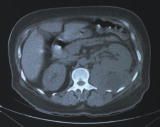

You order a CT scan of the abdomen.

The CT scan shows a large hypodense lesion associated with the lower pole of the left kidney. This finding, in conjunction with the hypoechoic density found on ultrasonography, strongly suggests

perinephric abscess, C.

Suspect this condition ina patient with uncontrolled diabetes and a history of nephrolithiasis and inadequately treated pyelonephritis who presents with fever and flank pain.